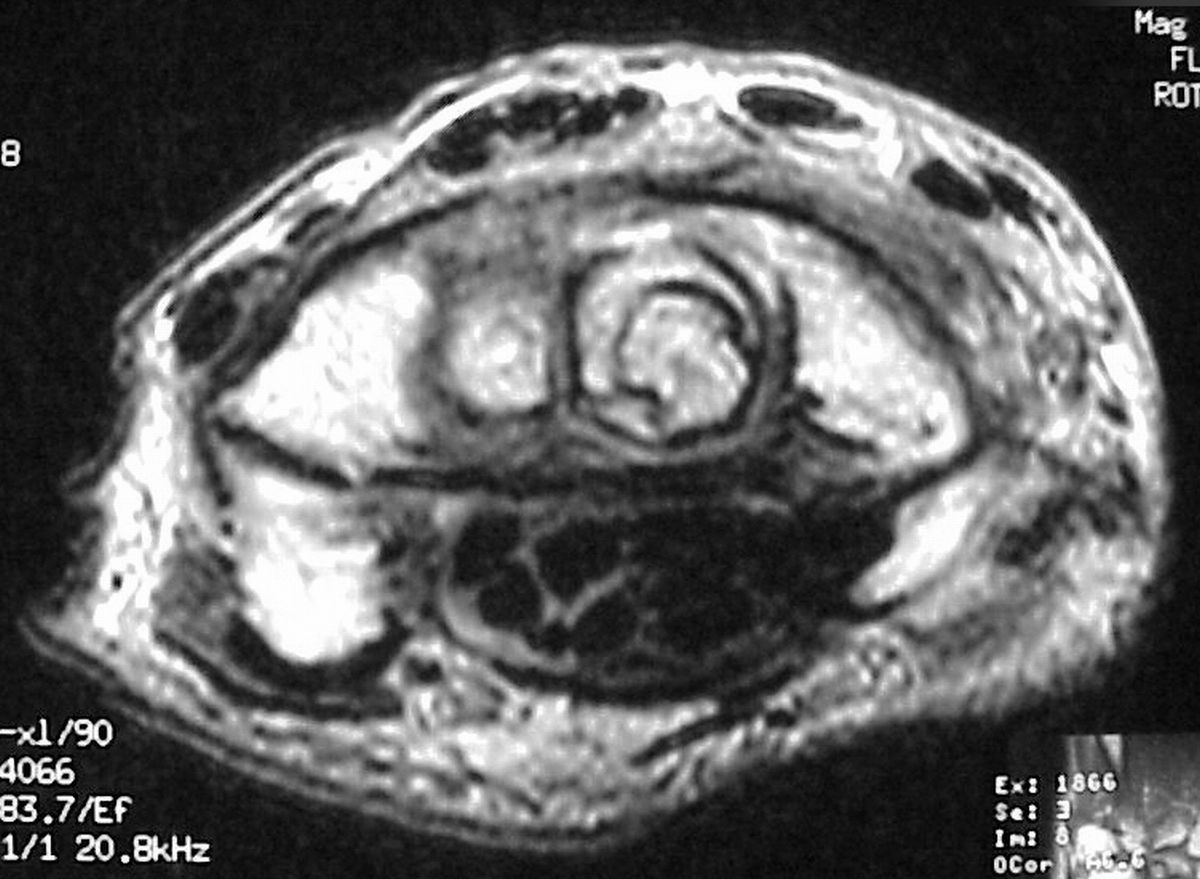

| MRI was

interpreted as inconclusive, differential including an

intraosseous cyst or giant cell tumor with cortical

thinning but no suggestion of malignancy. |